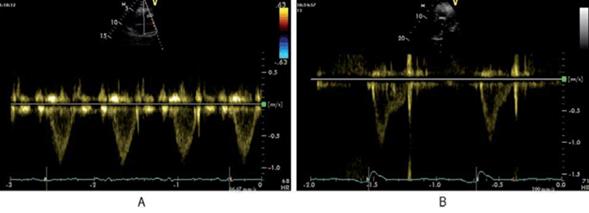

Flujo renal: se está investigando la evaluación de la PAD por Doppler del flujo renal en la insuficiencia cardíaca. Tang y colaboradores demostraron que la congestión venosa, con presiones derechas elevadas, altera el patrón de flujo venoso renal (normalmente continuo), haciéndolo pulsátil (discontinuo)23. El aumento de la PAD puede, entonces, manifestarse como un patrón bifásico durante cada ciclo cardíaco o por una disminución de la velocidad sistólica que evoluciona a un patrón monofásico diastólico, como se observa en la (figura 1)23. Los distintos patrones de flujo venoso renal se asocian pues con distintos niveles de PAD24.